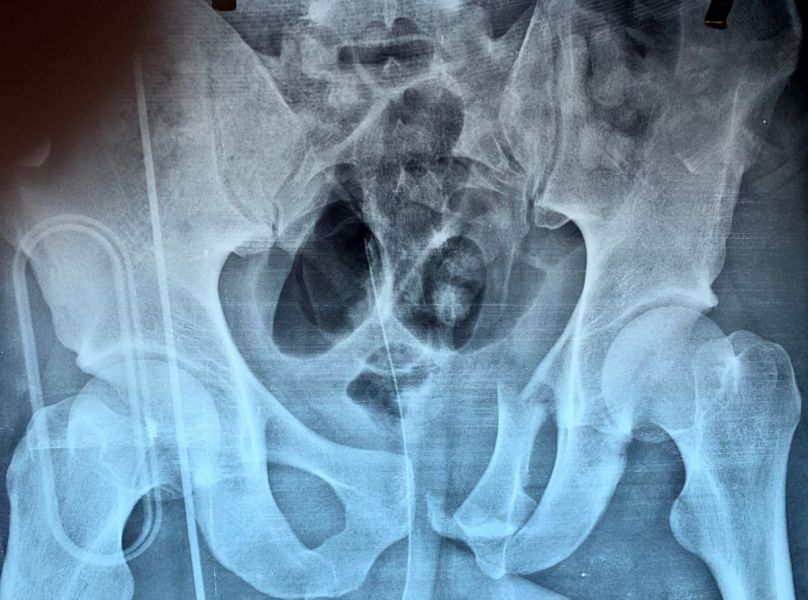

3. Pelvic fracture called also open book fracture in a 27-year-old male.

Treatment: Open reduction internal fixation of pubic symphysis and percutaneous fixation of the left sacroiliac joint

I. Before surgery II. Post-surgery, anteroposterior x-ray of pelvis showing one plate and six screws in pubic symphysis and one large screw in the left sacroiliac joint